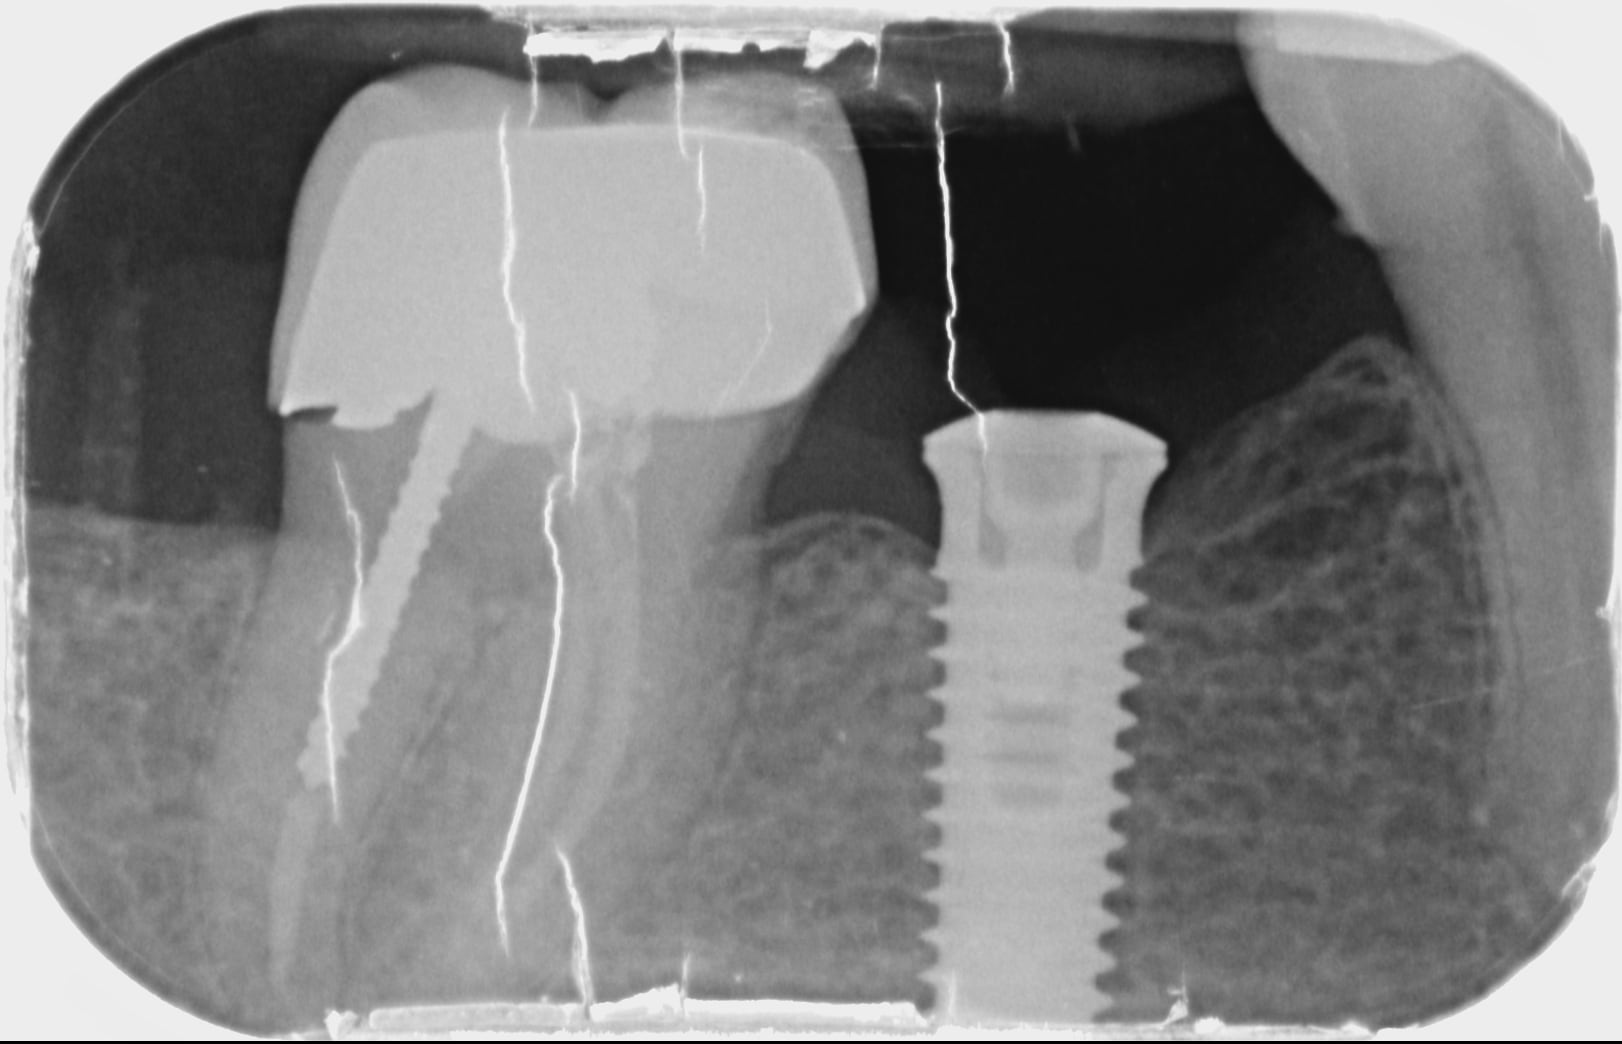

quelqu'un pourrait il me dire la marque de cet implant ?